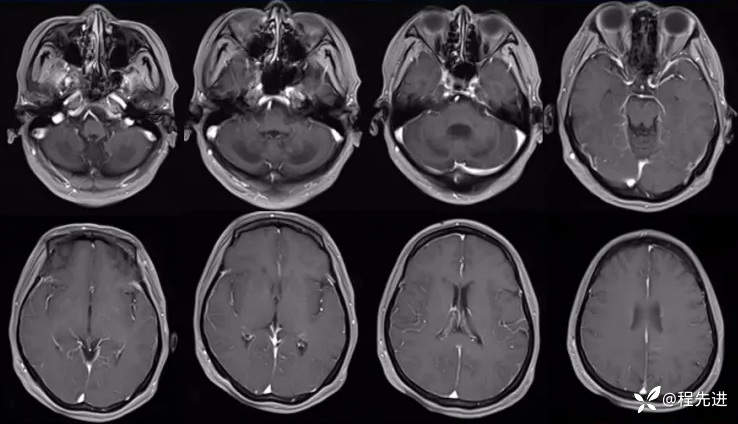

增强: